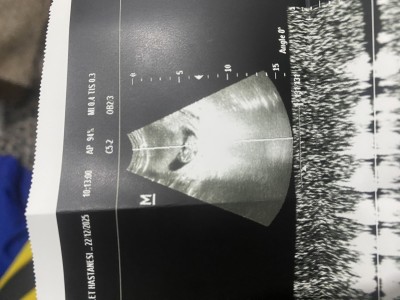

Merhabaaa hanımlar Keseye göre cinsiyet tahmini yapabilen var mı Çok merak ediyorum 10+5 günlük hamileyim